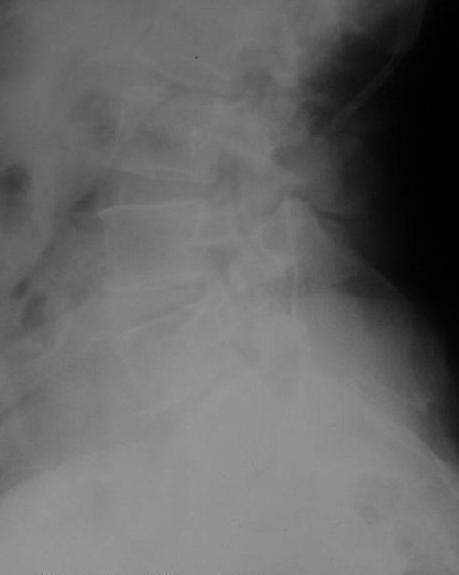

Крайне желательно выполнить МРТ поясничного отдела, так как на представленных рентгенограммах складывается впечатление о спондилолистезе L5,котрый наиболее вероятно и является причной болевого синдрома. Кроме того у болной имеется высокий риск гнойного поражения позвоночника. Только после МРТ можно планировать коррекцию вторичной деформации позвоночника.

Снимок поясничного отдела плохо просматривается на моем компе. Нет ли там спондилолистеза L5-S1?

Если есть, то операция на бедре не поможет. Если нет то есть вопрос - в каком положении контрактура?

После корригирующей остеотомии сохранится чрезмерная нагрузка на поясничный отдел за счёт анкилоза т/бедр. сустава.На фоне остеохондроза,спондилёза,спондилоартроза и спондилолистеза устранение порочного положения не избавит от болей и вряд-ли даже уменьшит их.Мне кажется тут нет альтернативы эндопротезированию.Но даже в этом случае не исключено,что позднее, на повестке появится необходимость вмешательства на позвоночнике.

Учитывая отсутствие жалоб со стороны тазобедренного сустава - оперативое лечение вряд ли принесет позитивный результат. На первый план выступает спондилолизный спондилолистез (вниматльно посмотрите снимки поясничного отдела)L5 позвонка. На наш взляд больному рекомндовано выполнить транспедикулярную коррекцию и фиксацию сегментов L4-S1 с установкой кейджа в L5-S1.